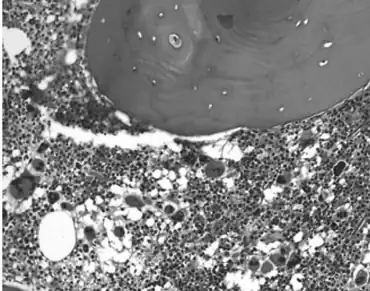

Essential thrombocythemia (ET) is a rare chronic blood cancer (myeloproliferative neoplasm) characterised by the overproduction of platelets (thrombocytes) by megakaryocytes in the bone marrow.[1] It may, albeit rarely, develop into acute myeloid leukemia or myelofibrosis.[1] It is a type of myeloproliferative neoplasm (blood cancers) wherein the body makes too many white or red blood cells, or platelets).[1]